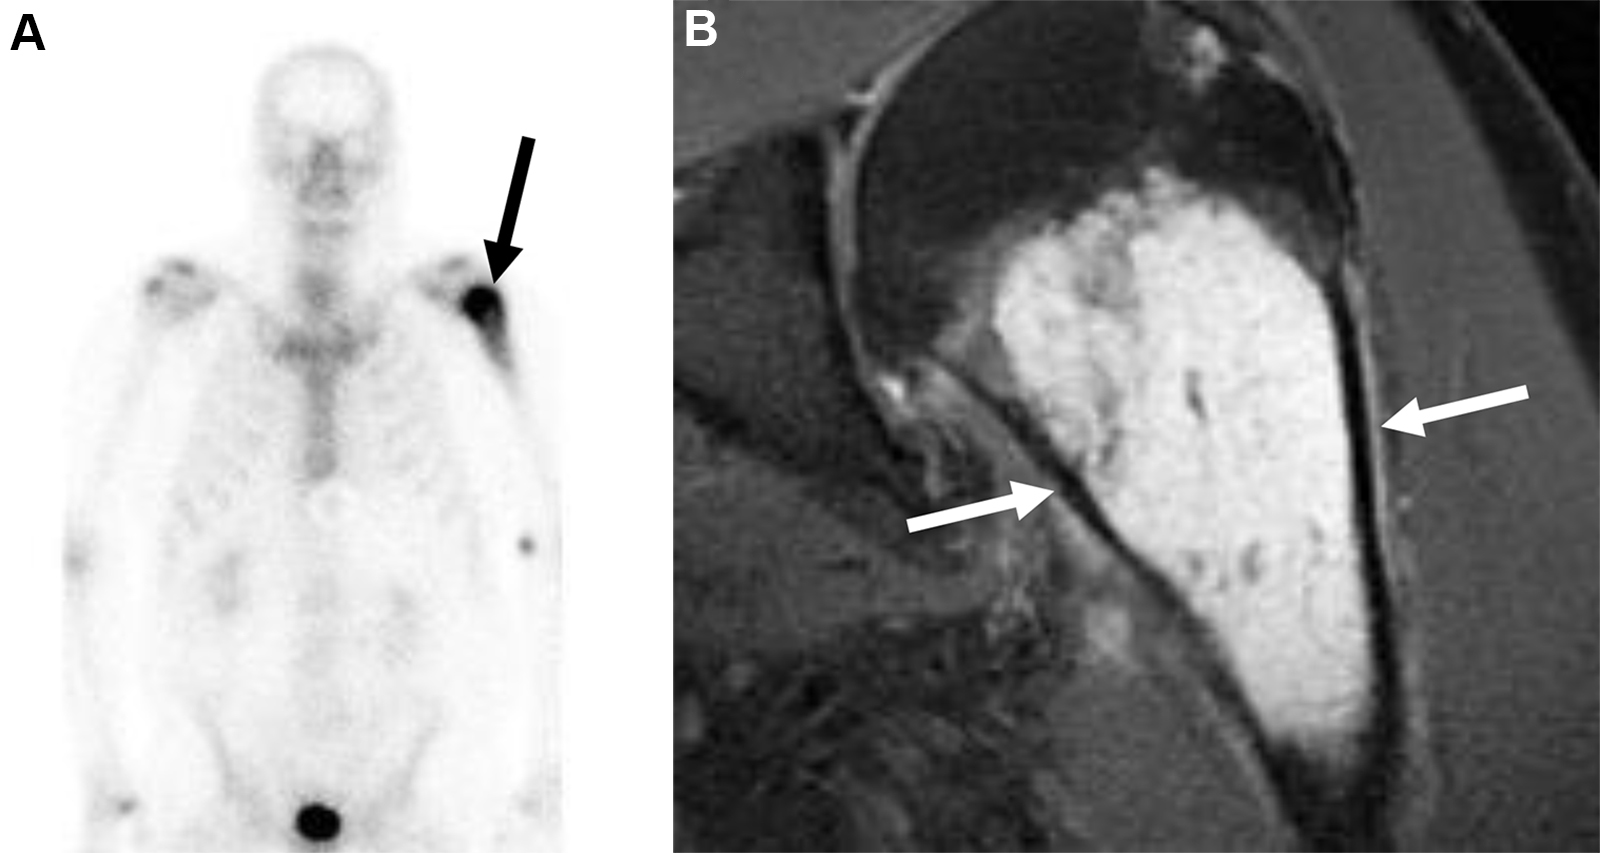

Metastasi costali e pleuriche con versamento pleurico in una donna di 63 anni con tumore al seno.

La scintigrafia ossea con 99mTc-MDP evidenzia una lieve ipercaptazione diffusa che ricalca l’emitorace destro, causata verosimilmente dall’accumulo di tracciante nel liquido pleurico maligno. È inoltre visibile una captazione longitudinale a carico dell’arco posteriore dell’XI costa destra. La TC conferma la natura della captazione, evidenziando il versamento pleurico, un ispessimento pleurico e le iniziali alterazioni osteosclerotiche a carico della costa interessata. Il caso dimostra come la scintigrafia ossea possa rilevare non solo le localizzazioni secondarie scheletriche dirette, ma anche segni indiretti di patologia extra-ossea adiacente (come la captazione pleurica).